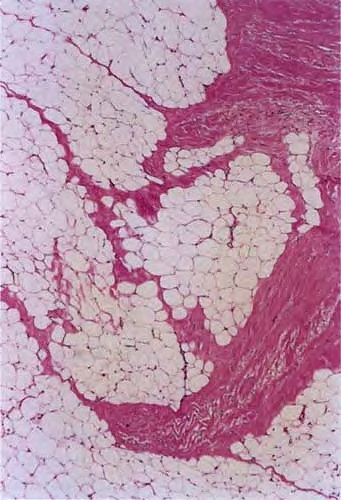

morphea